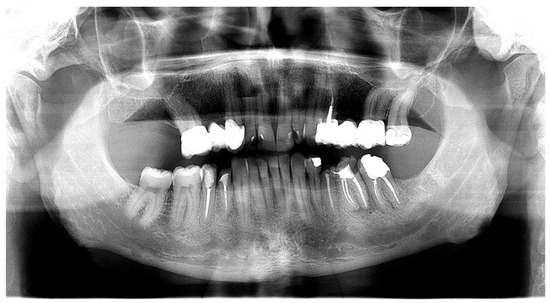

Oral Manifestations of Vitamin C Deficiency